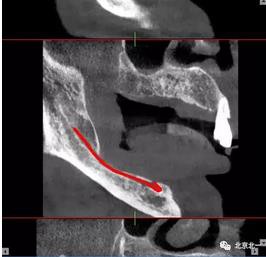

術(shù)前檢查片下頜骨季度萎縮,右側(cè)下頜下牙槽神經(jīng)管幾乎位于牙槽嵴頂。不能行常規(guī)種植。采用A04技術(shù)可實(shí)現(xiàn)即即刻種植一日戴牙夢(mèng)想。

圖一至圖六明顯看出右側(cè)頦孔位于牙槽嵴頂。很清晰看出頦孔區(qū)的U型形狀。